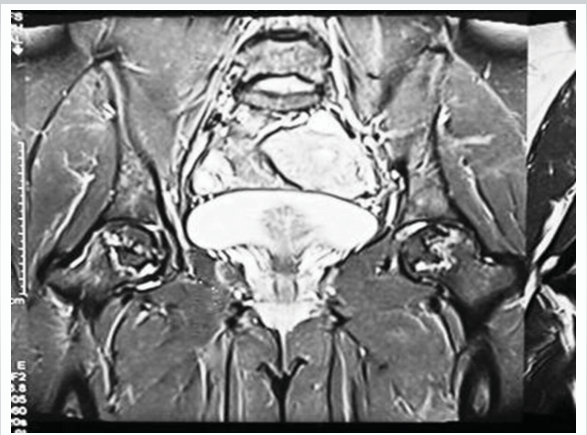

There was bilateral ON of the hips (stage 2 of Ficat-Arlet classification [8]) with greater involvement of the right femoral head than the left (Fig. 2).

Figure 2: Pre op MRI both hips. 1.5 T. Short tau inversion recovery coronal image showing ill defined geographic hyperintensities (right > left) in femoral head, femoral contour, and joint space maintained. Suggestive of avascular necrosis of both femoral heads (Ficat-Arlet II) (Right > Left).